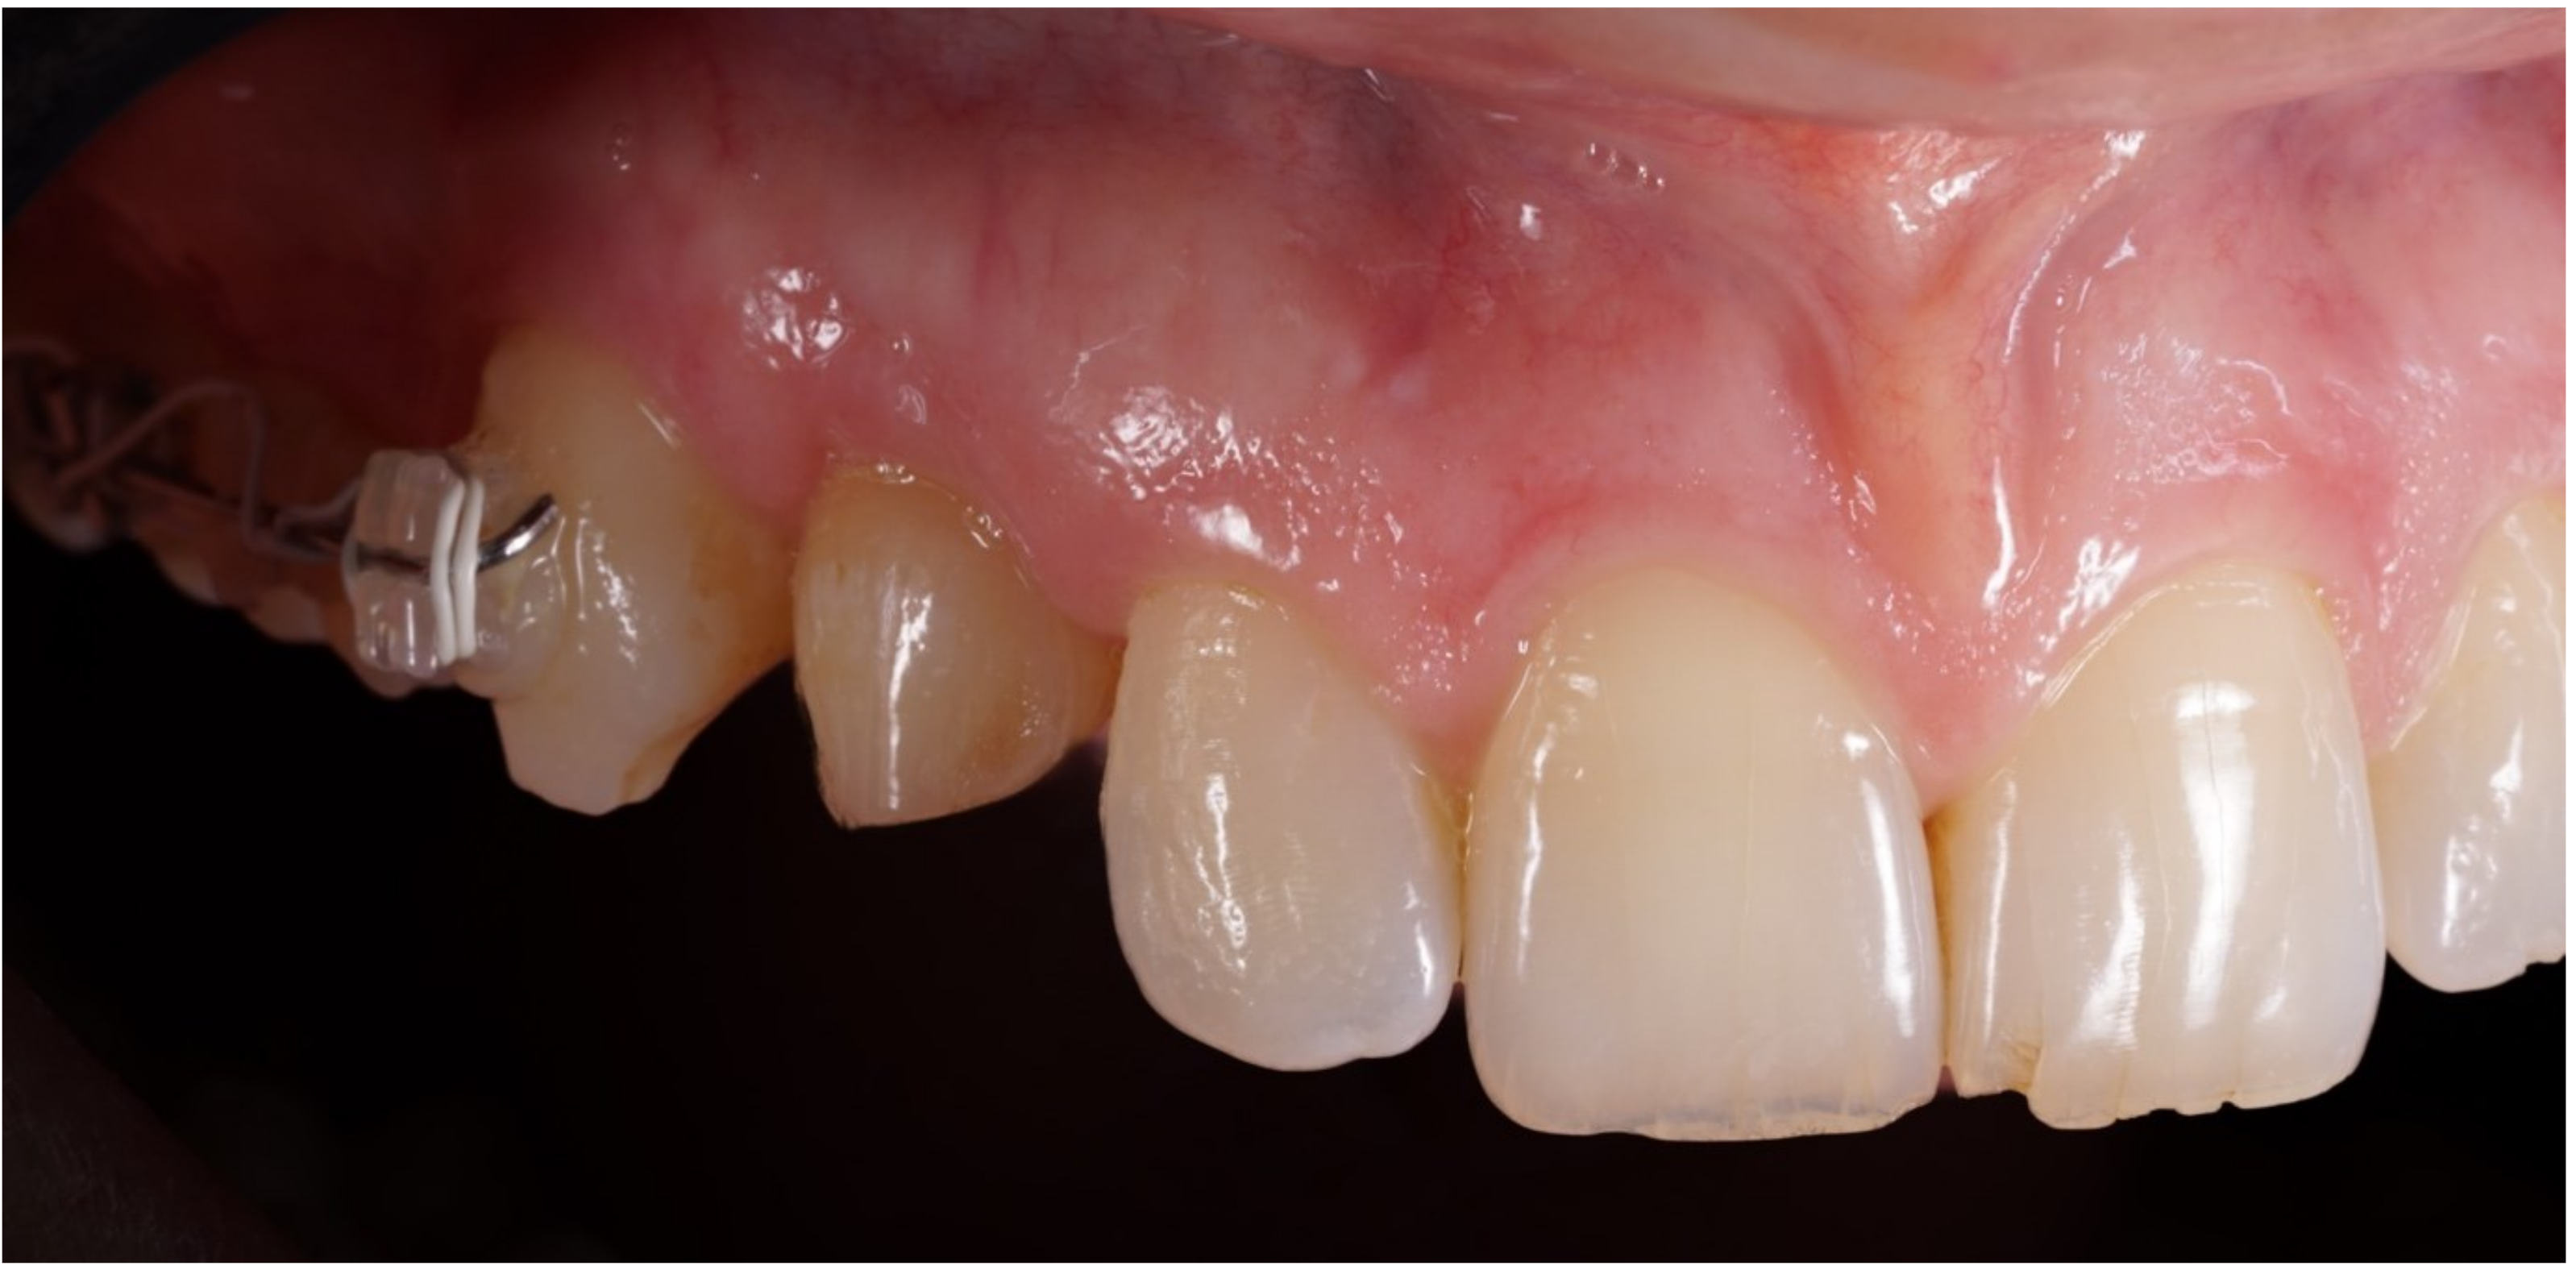

Figure 2.

Lateral preoperative view.